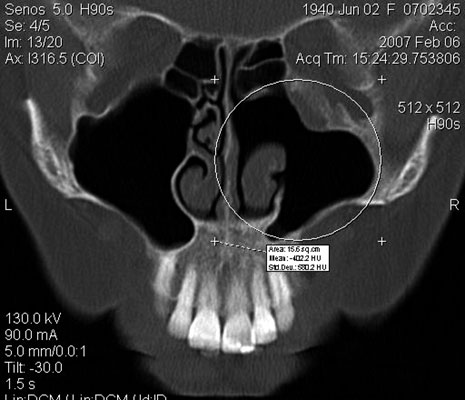

TC exostosis occipital congénica.

TC exostosis occipital congénita.